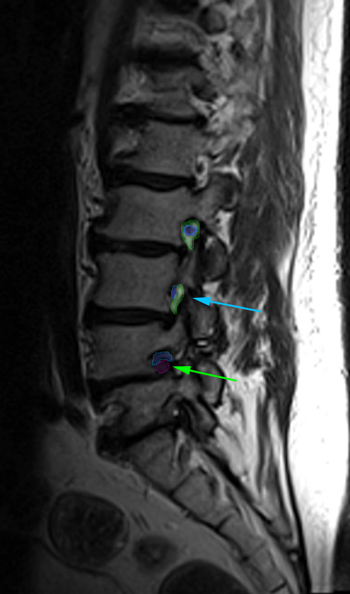

|

Αριστερά: Στένωση οσφυϊκού σπονδυλικού σωλήνα. Δεξιά:Φυσιολογικό νευρικό τρήμα στην κορυφή (πράσινο) με ελεύθερο νεύρο στο κέντρο (μπλέ περίγραμμα). Στενό τρήμα (κυανό βέλος) και ουσιαστικά κλειστό τρήμα,το οποίο εμπεριέχει μόνο το πιεσμένο νεύρο (πράσινο βέλος). Τεμάχιο δισκοκήλης εντός του τρήματος (κόκκινο περίγραμμα). |